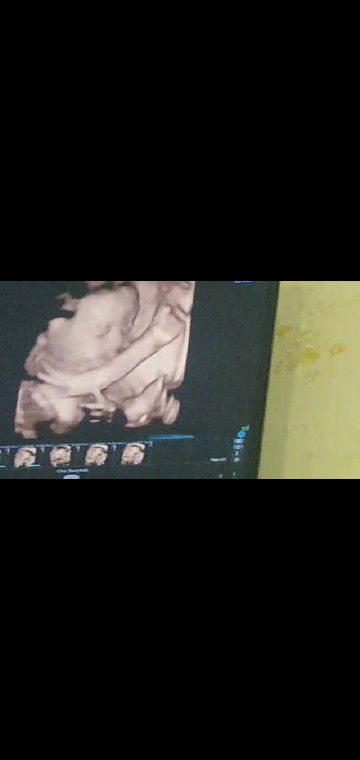

26week

MasyaAllah tabarakallah.. Dikasih kaki sm dede.. Tp abs itu dia โ??

Tangan nya kaya peace ,,dua jari gitu